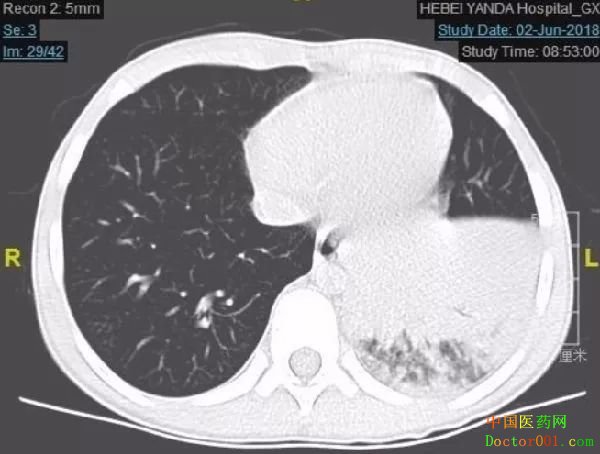

住院后,经胸部CT进一步检查后,显示小彬的肺部有大片实变影,且有大量胸腔积液,最终确诊为大叶性肺炎。

“他刚开始咳嗽时,症状很轻,没有引起重视,拖了一周后开始发烧我才开始着急”,小彬的妈妈愧疚的说。据小彬的责任医师刘洪飞介绍,小儿肺炎多是支气管肺炎、毛细支气管肺炎等小叶性肺炎,这种大片性肺炎相对少见。如果控制不好,里面可能会形成坏死、空洞,肺组织就坏了,如不及时治疗将会危及生命,后果不堪设想。

李红日主任立即调整治疗方案,在抗感染联合治疗的同时,因患儿有严重脓毒症症状,且有胸腔积液,完善肺结核检查除外肺结核的情况下,及时给予短期激素治疗。就这样,在李主任的精准判断与治疗下,第二天,小彬的体温明显下降,第三天体温便恢复正常,肺炎终于得到了控制,免疫功能复查也恢复了正常。